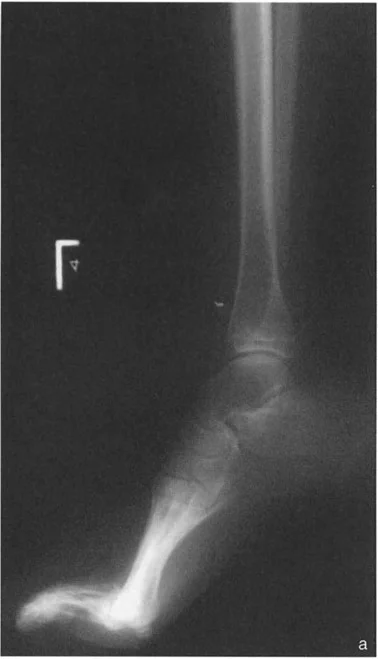

* الأشعة السينية الجانبية والامامية الخلفية للكاحل: تُظهر هذه الصور تفاصيل مفصل الكاحل نفسه، بما في ذلك زاوية القصبة الأمامية البعيدة (ADTA) وزاوية القصبة الوحشية البعيدة (LDTA)، وهي زوايا حاسمة لتحديد التشوه في المستويين الأمامي والسهمي.

* منظر سولتزمان (Saltzman View): هذا المنظر الإشعاعي الخاص يتم الحصول عليه بزاوية 20 درجة لقياس محاذاة عظم العقب (Calcaneus) بالنسبة لقصبة الساق، وهو أمر بالغ الأهمية لتقييم تعويضات القدم الخلفية.

أنواع جراحات قطع العظم فوق الكاحل (Supramalleolar Osteotomy)

جراحة قطع العظم فوق الكاحل (SMO) هي الإجراء الأكثر شيوعًا لتصحيح تشوهات قصبة الساق البعيدة. تتضمن هذه الجراحة قطعًا دقيقًا في عظم الساق (القصبة) فوق مفصل الكاحل مباشرة، ثم إعادة محاذاة العظم وتثبيته في الوضع الصحيح. هناك عدة أنواع من هذه الجراحة: